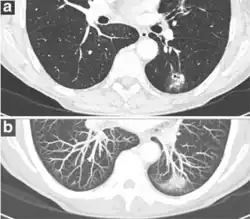

CT scan

For incidentally detected nodules on CT scan, Fleischner Society guidelines are given in table below. For multiple nodes, management is based on the most suspicious node.[8] These guidelines do not apply in lung cancer screening, in patients with immunosuppression, or in patients with known primary cancer.[8]